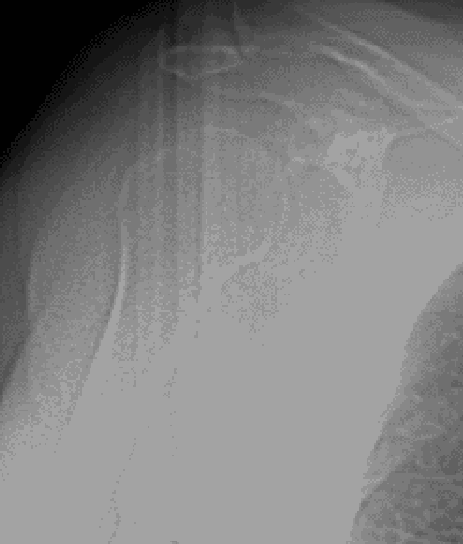

One of LINK’s major objectives in joint arthroplasty is the preservation of vital bone. In the LINK Embrace Shoulder System, Humeral Short Stems as well as Stemless Cages help to save valuable bone stock for possible future treatments and revisions. For stemless primary reverse arthroplasty, the LINK Embrace Shoulder System offers Stemless Ring Cages, designed for direct connection to the required Reverse Insert. Stemless Ring Cages may also be used for anatomic reconstruction with both Humeral Heads and CTA Heads by means of specific adapters. Bone contact areas of LINK Embrace Stemless Cages and Stemless Ring Cages are equipped with a TrabecuLink surface, aiming at good primary stability as well as fast and long lasting bony integration.1